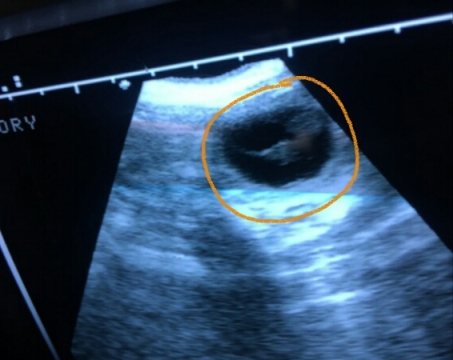

Daka ist tragend!

Die S-Welpis sind also auf dem Weg - wir freuen uns so!

Hier die ersten "Fotos" der Kleinen.